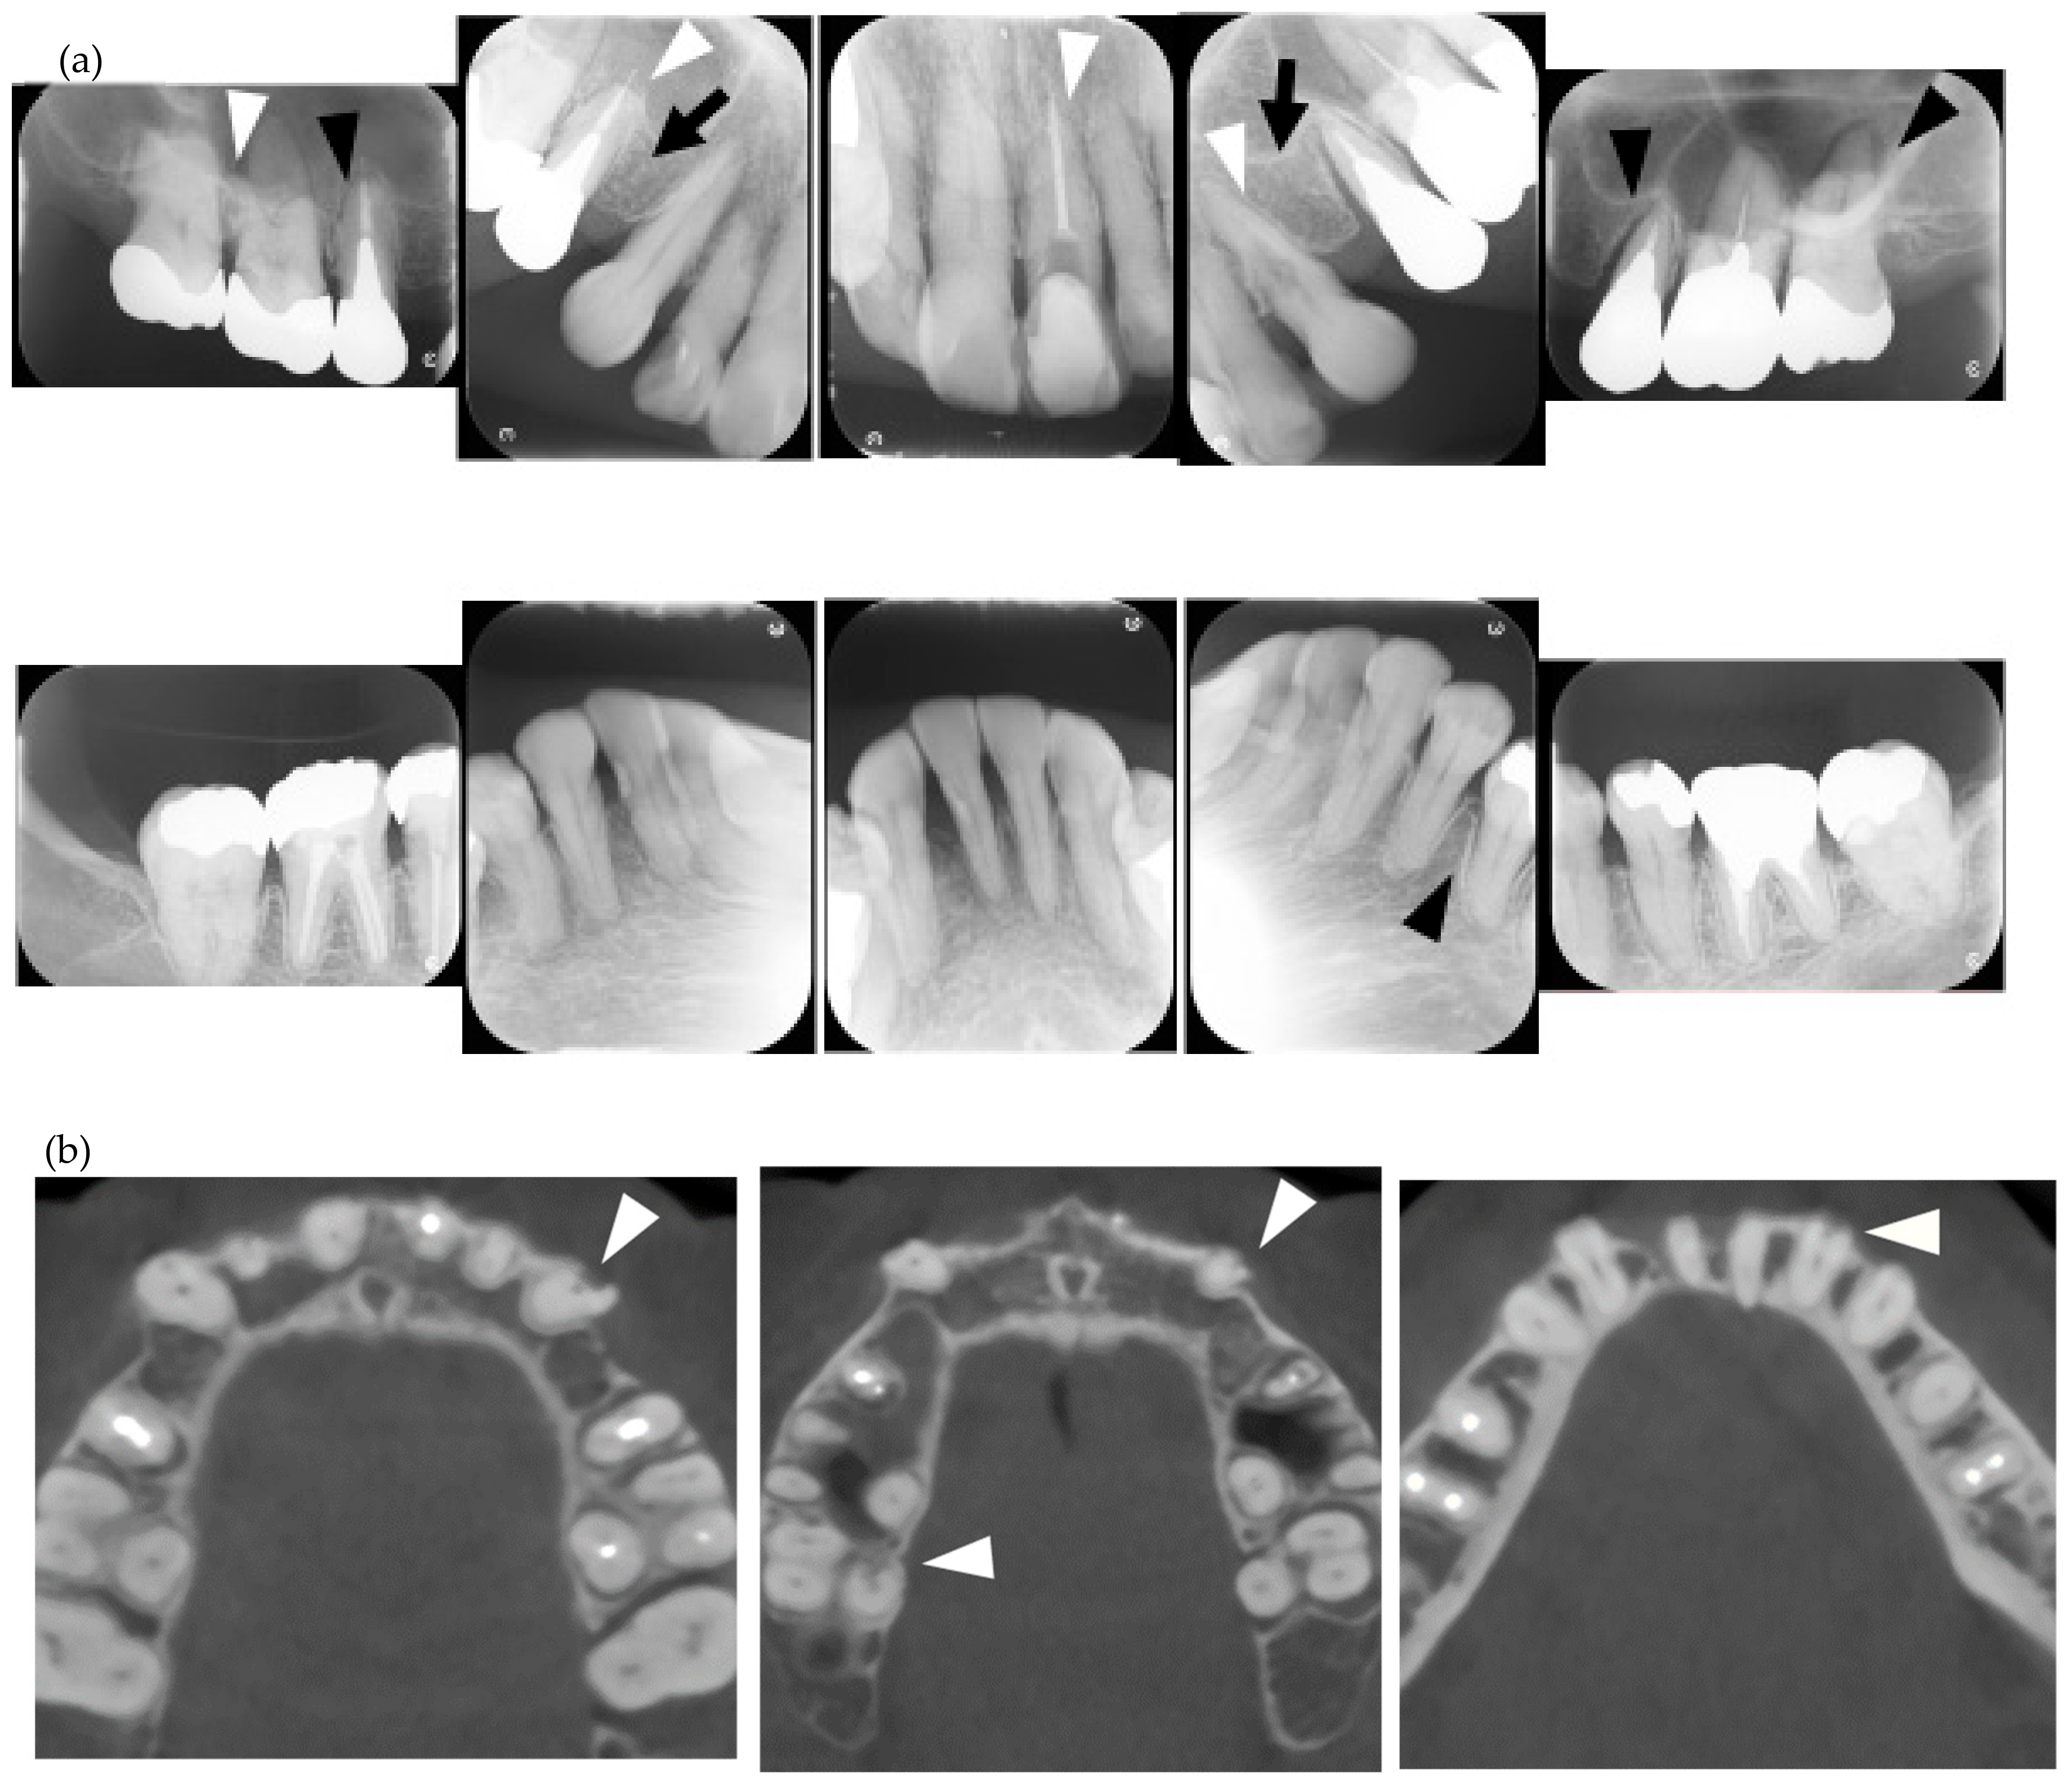

| PDL space widening | 35 (85.4) |

| 1 | F | 24 | lc | Y | Y | N | Y | Y | Y | Y | Y | Y | Y | / | / | / | Y | Y | N | Y | Y | Y | N | centro/RF | a case report [6]/occlusal force, 77.4N |

| 2 | F | 40 | dc | Y | Y | Y | Y | N | N | N | Y | N | Y | / | N | N | Y | Y | Y | Y | N | Y | Y | Scl-70/RF | |

| 3 | F | 23 | dc | Y | Y | Y | Y | N | Y | N | Y | Y | Y | / | / | / | Y | Y | Y | Y | Y | Y | Y | ANA/Scl-70/SS-A | Orthodontic treatment |

| 4 | F | 11 | dc | Y | Y | Y | Y | Y | N | N | N | N | Y | / | / | / | Y | Y | Y | N | N | Y | Y | ANA/Scl-70 | calcification in PDL space/Orthodontic treatment |